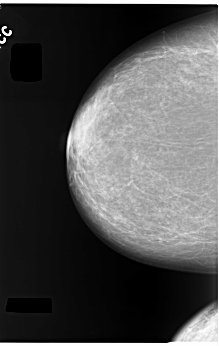

C_0055_1.LEFT_CC

FILE: C_0055_1.LEFT_CC.OVERLAY

TOTAL_ABNORMALITIES 1

ABNORMALITY 1

LESION_TYPE CALCIFICATION TYPE PLEOMORPHIC DISTRIBUTION SEGMENTAL

ASSESSMENT 5

SUBTLETY 5

PATHOLOGY MALIGNANT

TOTAL_OUTLINES 1

BOUNDARY